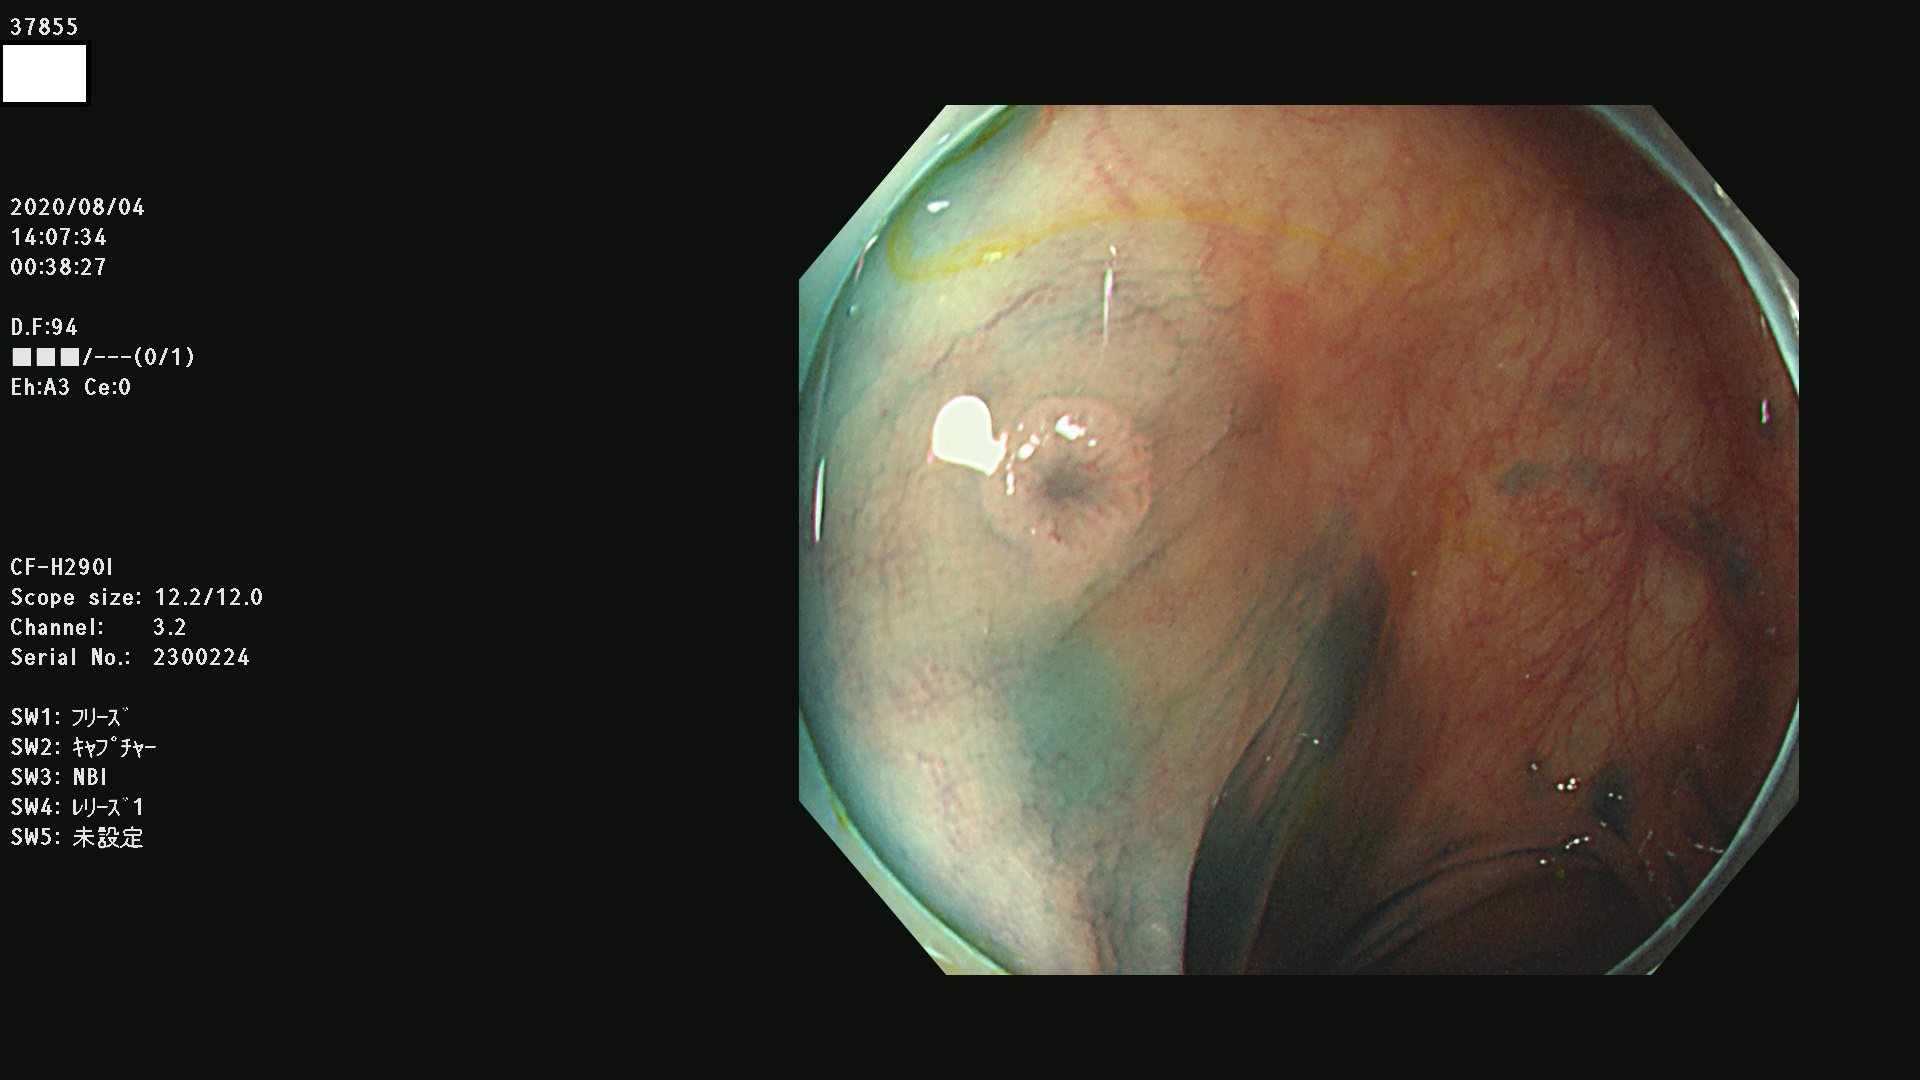

腺腫発見率 75 % (カルテ番号 37800〜37899の100名の方の検査結果で集計)大腸癌検診最新情報

以下のカルテ番号の方に腺腫(Adenoma,Group3〜5)が見つかりました(集計法)

37800(SSAPのみ) 37801 37802 37803 37804 37805 37806 37807 37808 37809(SSAPのみ) 37810 37811 37812 37813 37814 37815 37817 37818 37819 37820 37821 37822 37824 37825 37826 37827 37828 37829 37832 37833 37836 37837(SSAPのみ) 37839 37840 37842 37844 37845(SSAPのみ) 37847 37849 37850 37851 37852 37853(SSAPのみ) 37855 37856 37857 37860 37861 37862 37863 37864 37867 37868 37871 37874 37876 37877 37879 37880 37881 37882 37883 37886 37887 37888 37889 37890 37891 37892 37893 37894 37896 37897 37898 37899

発見困難で危険性の高い平坦型病変(上記100名より抽出) ![]()